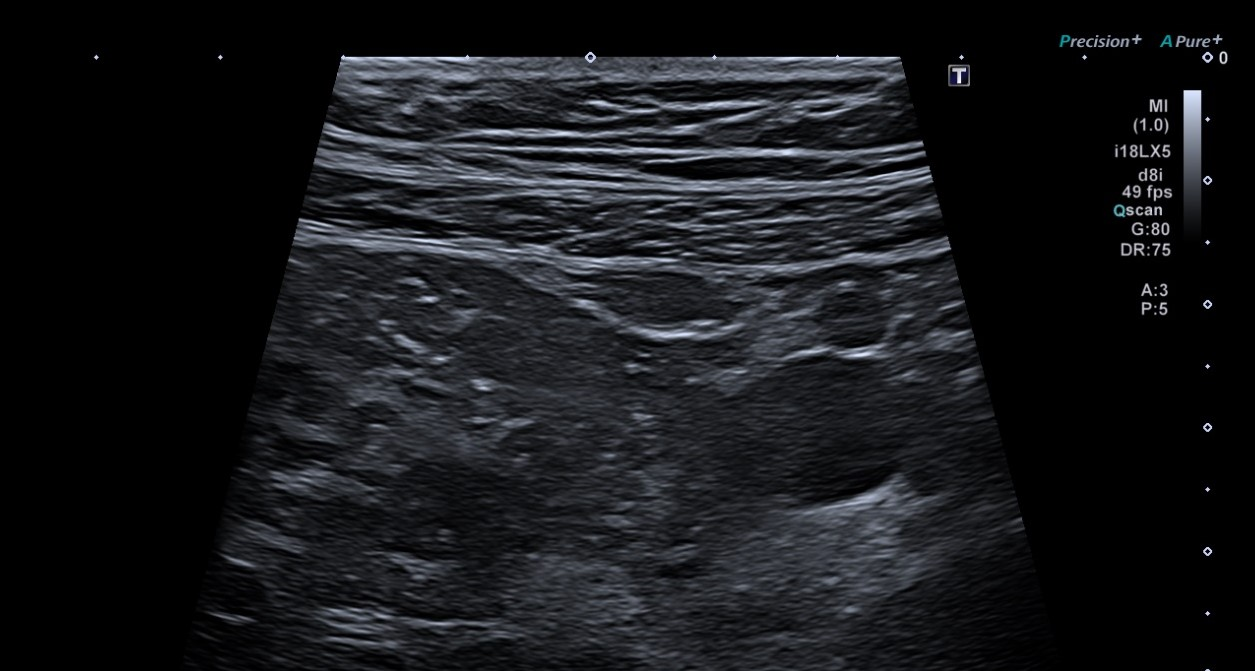

Ecografía partes blandas: En localización infraumbilical, sin aparente dependencia de estructuras profundas ni modificación en maniobra de Valsalva, lesión hipoecoica bilobulada (4,3 x 8,5 x 7,1 mm) con aparente conexión hacia región vesical, sobre la que no se demuestra vascularización, inespecífica, que podría corresponder a seno uracal, sin poder descartar sobreinfección asociada.